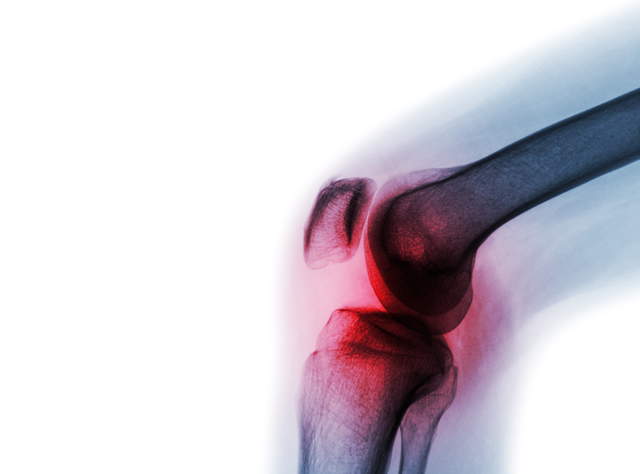

Rheumatic disease can present in a number of ways including joint pain, stiffness, inflammation causing joint swelling and other symptoms such as rashes, fatigue, back pain and weakness.

Conditions include those caused by autoimmunity such as Rheumatoid Arthritis. This is a chronic, painful and potentially debilitating condition which can cause joint pain and swelling and, in severe cases, deformities. Early diagnosis is critical and treatments can prevent long-term disability.